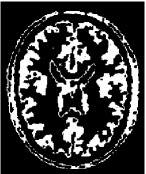

4.2 Inhomogeneous image segmentation

In this subsection, we extend our proposed method to segment two classes of inhomogeneous images shown in Figure 4.6. The left is a synthesized image by combining the arterial blood vessels of a human head. The right is a MRI brain image based on an anatomical model of normal brain from the slice 91 of the normal brain database, which is available to the public at http://www.bic.mni.mcgill.ca/brainweb/. Here we set as “modality=T1, Slice thickness=1mm, intensity non-uniformity = 20%” for the original image 4.6(b). Different to the numerical comparisons of the piecewise constant image, we do not know the real segmentation due to the inhomogeneity. So we except to obtain a better restored image as the stopping condition in the first step of our proposed strategy.

Refer to caption

(a) Synthesis Image

(b) MRI Image

Figure 4.6: The original images in Example 4.3 and 4.4.